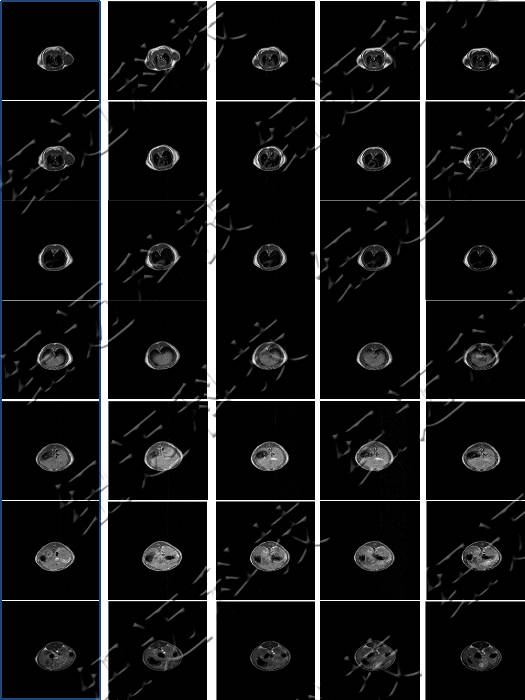

測試釓類MRI造影劑弛豫率測試以及造影劑樣品的T1加權(quán)成像。

弛豫效率是MRI造影劑關鍵指標之一。

造影劑:通過內(nèi)外界弛豫效應和磁化率效應間接地改變組織信號的強度,以增加組織或器官對比度的一類物質(zhì)。

核磁共振成像(MRI)目前普遍應用于醫(yī)學檢測成像中,具有無輻射損傷的安全性,可任意方位斷層掃描等技術靈活性,加以涵蓋質(zhì)子密度、弛豫、加權(quán)成像以及多參數(shù)特征的優(yōu)勢,已成為當代臨床診斷中最有力的檢測手段之一,然而臨床發(fā)現(xiàn)某些不同組織或腫瘤組織的弛豫時間相互重疊,導致診斷困難。